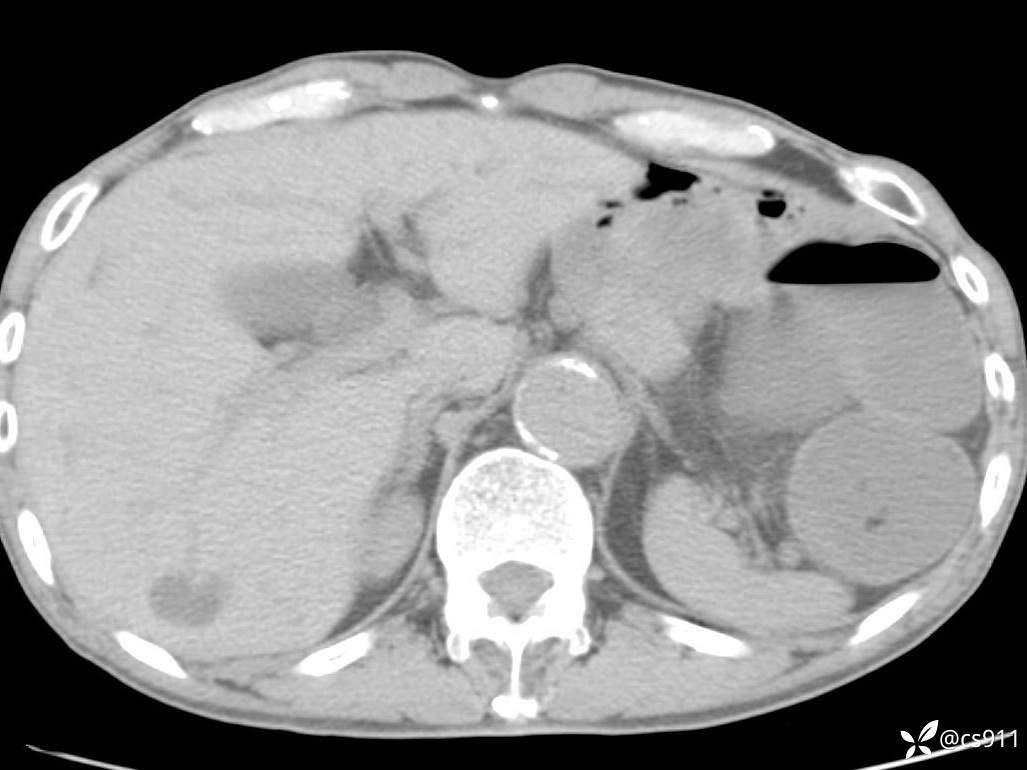

急腹症之急诊CT,原因?答案公布

男,77岁,腹痛、腹胀伴恶心呕吐1天。呕吐胃内容物,非喷射性呕吐,有咖啡色样胃内容物,诉有胃穿孔病史。查体:全腹平,下腹部压痛,全腹无反跳痛,叩诊呈浊音,移动性浊音阴性,肠鸣音减弱,1-2次/分。肛检:直肠未扪及明显肿物,可触及大量粪块。

T 36.6℃ P 80次/分 R 26次/分 BP 100/60mmHg

白细胞(WBC) H 14.55 10e9/L 4-10

中性粒细胞百分率(NEUT%) H 85.7 % 40-75

血淀粉酶(AMY) HH 1859 U/L 35-135

癌胚抗原(CEA) H 27.44 ng/ml 0-5

呕吐物 潜血试验 * 阳性 阴性

患者轮椅入室检查神志清楚, 能配合摆位和呼吸